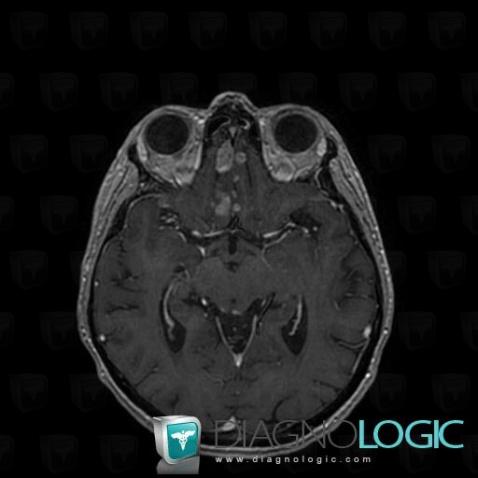

Voici les informations spécifiques à l'image clé ci dessus:

- Diagnostic Méningite carcinomateuse, Localisation(s) Région cortico sous corticale, comportant les gammes Lésion corticale

Voici les informations spécifiques à l'image clé ci dessus:

- Diagnostic Méningite carcinomateuse, Localisation(s) Espaces peri cérébraux infratentoriels, comportant les gammes Lésion extra axiale infra tentorielle

Voici les informations spécifiques à l'image clé ci dessus:

- Diagnostic Méningite carcinomateuse, Localisation(s) Espaces peri cérébraux infratentoriels, comportant les gammes Anomalie des citernes de la base